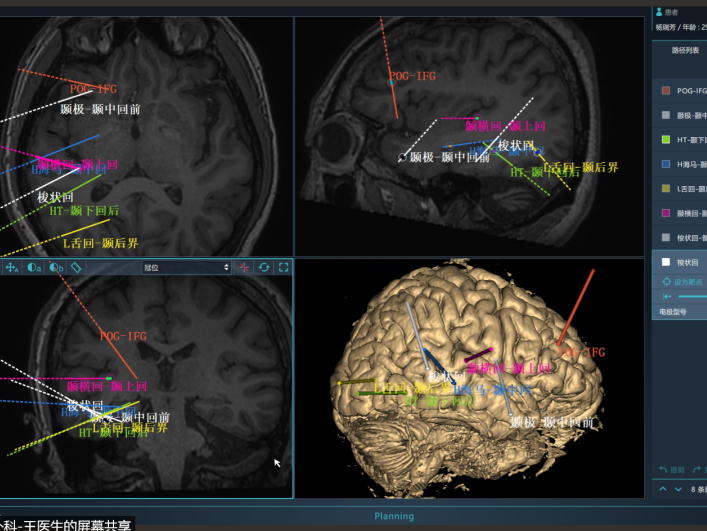

郑州大学五附院癫痫治疗专科在神经外科学科带头人王新军教授带领下已经发展20余年,并于2012年由河南省卫生厅授予“河南省癫痫病系统化诊疗中心”委托单位。癫痫专科团队逐渐壮大,学科团队由神经外科、神经内科、神经电生理科、儿科、儿童康复医学科、精神卫生科、放射影像科、病理科,药学部等多学科人员组成。河南省癫痫病系统化诊疗中心在王新军教授、单峤主任、吴艳芝主任带领下,得到了孙伟教授的悉心指导,郑州大学五附院癫痫诊疗团队多学科协作,致力于癫痫的发作及诊断分型,以及各种癫痫隐匿性病因的查询,引领医学前沿,开展生酮饮食疗法,开展立体定向脑电图(SEEG)精确定位致痫灶,开展顽固性癫痫外科治疗(获省科技进步奖),为癫痫患者癫痫控制和生活质量的提高提供全方位的服务,大大提高治疗效果,让患者更安心,更放心!